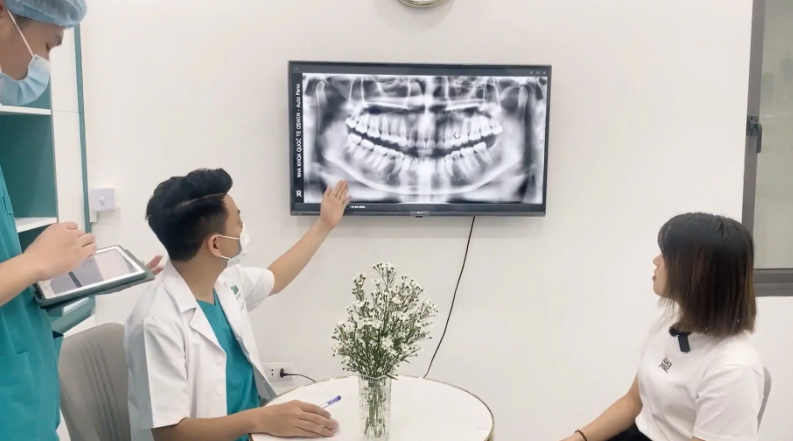

Tìm kiếm và đặt lịch bác sĩ, cơ sở y tế chuyên khoa uy tín.

Tìm kiếm địa chỉ, bác sĩ niềng răng giàu kinh nghiệm.